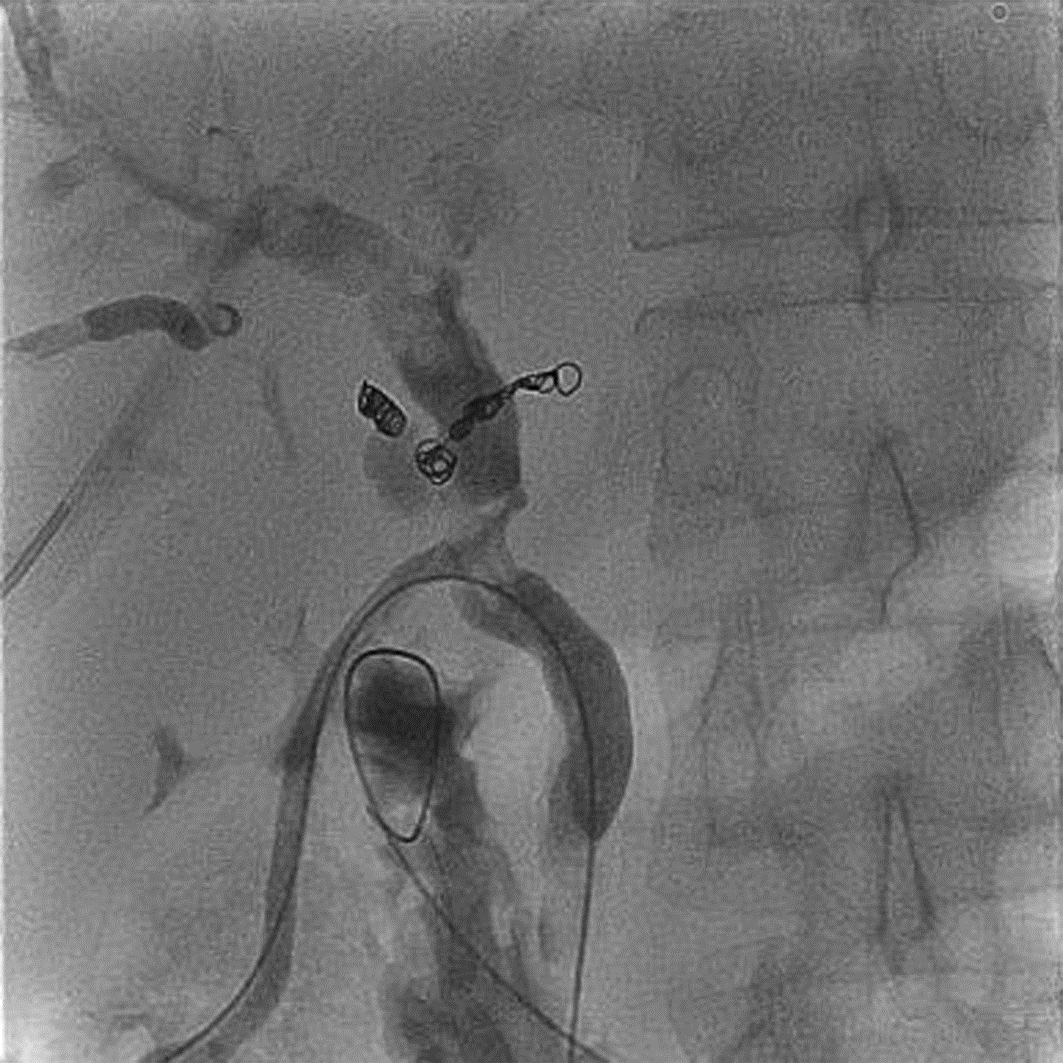

Diagnosis and treatment of hepatic pseudoaneurysm with bile leakage and bile duct hemorrhage after transplantation of donor liver with right hepatic artery variation: A case report

Tian HAN, Rui ZHANG, Zhiyong SHI, Li ZHANG, Jun XU

2022, 38(12): 2818-2820. DOI: 10.3969/j.issn.1001-5256.2022.12.024

Abstract(1759) HTML (1058) PDF (2268KB)(66)

Abstract: